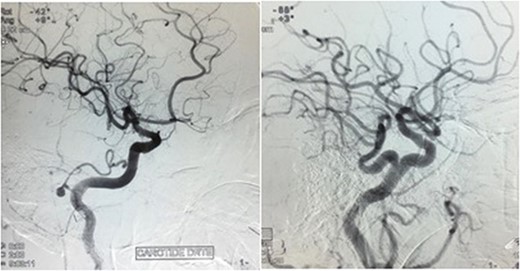

The angiography concluded to a persistent left trigeminal artery associated with a medious saccular aneurysm (4.8 × 4.6 mm) originating from a right posterior meningeal artery (Fig. 2).

Angiography showing medious saccular aneurysm (4.8 × 4.6 mm) taking origin from a PMA with the persistence of a left trigeminal artery.